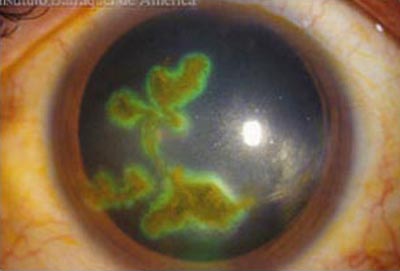

La forma más frecuente de la queratitis herpética es la ulcera dendrítica, que es una lesión lineal ramificada con bulbos terminales y bordes inflamados que contienen virus vivos. Se tiñe positivamente con fluoresceina lo que facilita su diagnóstico; compromete el epitelio pudiendo alcanzar la membrana basal en la etapa inicial. Produce sensación de cuerpo extraño, lagrimeo y visión borrosa.

Cuando la úlcera pierde su caracter lineal, se la conoce como “ ulcera geográfica” que representa a una lesión dendrítica extendida y se asocian a una mayor duración de los síntomas y con frecuencia al uso previo de corticoides.

Herpes Simple

Herpes Simple